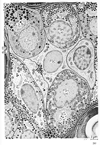

黄体【おうたい】 Gland arising from the corpus rubrum. Fat droplets lend it a yellow appearance. It is an endocrine gland that secretes progesterone and estrogen.(黄体は排卵後の卵胞から生ずるが、黄体細胞の起源は2通りあると考えられている。その大部分は顆粒層細胞から生じ、顆粒層黄体細胞(granulosa lutein cells)とよばれてる。ほかの種類は黄体の周辺部にある小さい細胞で、卵胞膜黄体細胞(theca lutein cells)とよばれる。黄体細胞は副腎皮質束状帯の細胞に似ていて、非常によく発育した滑面小胞体と多数の脂質滴を含み、糸粒体は球形の大型のものが多く、クリスタは管状である。粗面小胞体も平行板状に並んだ群が斑点状に分布する。黄体ホルモン(progesterone)はこのよく発達した滑面小胞体と糸粒体の共働のもとに合成されると思われる。そのほかに300nm前後の暗調な球形顆粒がみられることがあり、開口様式で放出される像が得られている。この顆粒は黄体から分布されるという蛋白ホルモンであるリラキシンではないかという説がある。)